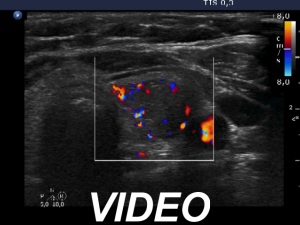

Ultrasonography. The thyroid was echonormal. There was a hypoechoic lesion in the left lobe. It was equivocal whether the lesion was composed of multiple nodules, therefore most of the lobulations seen on the surface of the mass were of questionable origin. However, there were protrusions in the ventral and medial part of the mass which were suspicious being pathological lobulations.